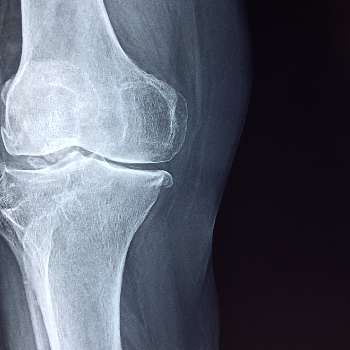

골다공증은 뼈의 밀도가 낮아지고 뼈 조직의 미세구조가 변형되어 뼈가 약해지는 질환입니다. 이로 인해 골절 위험이 증가하며, 특히 노인들에게 흔하게 발생합니다. 골다공증은 초기에는 특별한 증상이 없지만, 시간이 지남에 따라 다양한 증상이 나타날 수 있습니다. 여기에서는 골다공증의 주요 증상 10가지를 전문가적 관점에서 상세히 설명하겠습니다.

골다공증 증상5. 골절의 잦은 발생

골다공증 환자는 작은 충격이나 일상적인 활동 중에도 쉽게 골절을 경험할 수 있습니다. 이는 주로 손목, 고관절, 척추 등 부위에서 발생하며, 이러한 골절은 환자의 활동성을 크게 제한합니다. 골절 후에는 회복이 느리고, 재골절의 위험도 높아집니다. 이는 환자의 전반적인 삶의 질을 크게 저하시키며, 독립적인 생활을 어렵게 만듭니다. 특히 고관절 골절은 노인들에게 매우 위험하며, 수술 후에도 회복이 어려운 경우가 많아 장기적인 침상 생활로 이어질 수 있습니다.

골다공증 증상6. 관절 통증 및 강직

골다공증이 진행되면서 관절 주변의 뼈와 연골도 약해질 수 있습니다. 이는 관절 통증과 강직을 초래하며, 특히 아침에 일어날 때나 장시간 앉아 있다가 일어날 때 증상이 더 심해질 수 있습니다. 이러한 증상은 일상적인 움직임과 활동을 방해하고, 환자의 이동성을 제한합니다. 관절 통증은 특히 무릎, 엉덩이, 손목 등의 부위에서 흔히 발생하며, 이는 환자의 생활의 질을 저하시킬 수 있습니다.